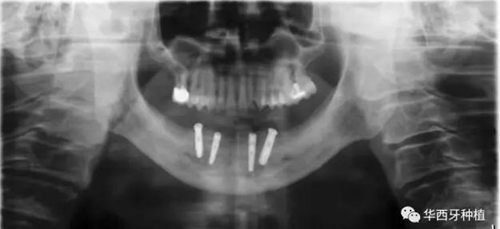

對于骨質較差的患者,種植覆蓋義齒修復與all-on-four或all-on-six修復,則更為適合。

吳教授特別針對手術難度更大的all-on-four修復做了詳細的關于概念、設計、操作、修復的描述,首先是針對難度最大的手術環(huán)節(jié),就解剖、微創(chuàng)操作分別加以闡述。將他自己在臨床工作中的寶貴經(jīng)驗分享給了大家。

對于傳統(tǒng)的all-on-four術式,吳教授加入了微創(chuàng)的指導思想,設計時同樣加入數(shù)字化三維重建與修復一體化設計,增加了手術的可控性,同時極大減輕了患者的創(chuàng)傷程度,縮短了修復周期。